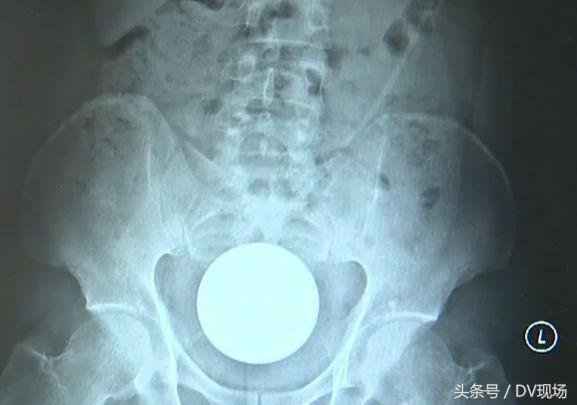

经腹部平片检查

在小明的盆腔处有一较大圆形物

由于异物较大,超过肛门大小

无法从肛门自行排除